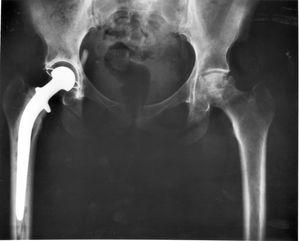

- 이식 장치: 생체 구조를 대체하고 기능을 수행하는 의료 기기를 개발하는 분야이다.

3. 9. 2. 이식 장치 (Implants)

임플란트는 생체 구조를 대체하고 그 기능을 수행하도록 만들어진 일종의 의료 기기이다(생체 이식 조직을 의미하는 이식과는 대조적).[12] 신체와 접촉하는 임플란트 표면은 티타늄, 실리콘, 아파타이트와 같은 생체 재료로 만들어질 수 있다. 일부 경우 임플란트에는 인공 심장 박동기 및 인공 와우와 같은 전자 장치가 포함되어 있다. 일부 임플란트는 이식형 알약 또는 약물 방출 스텐트 형태의 피하 약물 전달 장치와 같이 생체 활성적이다.3. 9. 3. 생체 공학 (Bionics)

| 3등급 | 기기의 안전성과 효율성을 보장하기 위한 과학적 검토가 필요하다. | 교체용 심장 판막, 엉덩이 및 무릎 관절 임플란트, 실리콘 젤 충전 유방 임플란트, 이식형 소뇌 자극기, 이식형 심장 박동기 펄스 발생기, 골내 임플란트 |